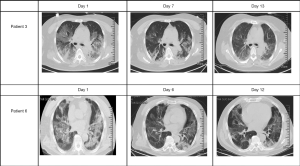

CT images after use of Tocilizumab

All patients had typical symptoms of bilateral pneumonia before medication. The CT imaging of Patient 3 and Patient 6 was reviewed about 1 week after medication, showing reduced inflammatory lesions (Figure 4). Patient 1 died three days after starting treatment, while Patient 2 died four days after. Patients 4 and 5 were placed on continuous mechanical ventilation, so they did not have a follow-up CT scan.

Among the six critically ill patients in this cohort, all had a severe respiratory infection requiring mechanical ventilation support. Several studies have observed the potential role and value of anti-inflammatory strategies in the treatment of COVID-19, but few related clinical studies assessed the impact of Tocilizumab, specifically. A clinical trial of Tocilizumab found that all 21 patients enrolled in the study improved after treatment, though only two patients were categorized as having severe disease (15). Similarly, another single-center study (16) reported that of 15 patients, ten showed decreasing levels of IL-6 after taking the medication. More so, of four patients who failed treatment, IL-6 continued to increase after medication, which was consistent with Patient 2 in this study. Our study also found that all six patients had improved clinical symptoms during the observation period after starting therapy, including reduced fever and improved heart rate and oxygen levels. The CT images of the lungs of the two patients discharged were improved. Thus, our study further builds upon these findings, highlighting the potential efficacy of using such therapy in those who may be sickest.